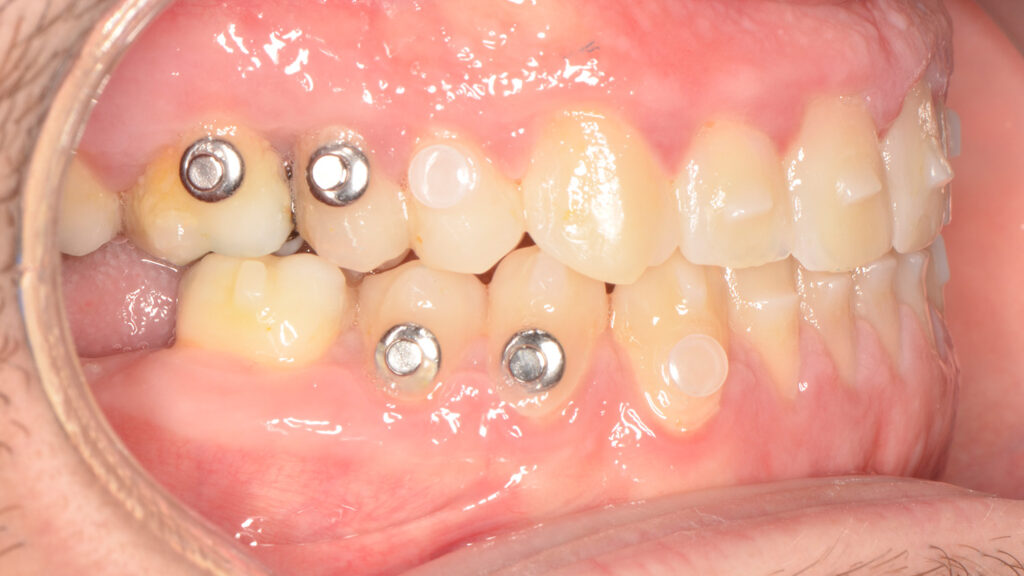

The patient was informed of various treatment options, including combined orthognathic surgery and orthodontic appliances. However, he opted against surgery. Consequently, a compensatory orthodontic treatment plan using MARPE (Mini-Implant Assisted Rapid Palatal Expander) and Spark Aligners was chosen, after the extraction of the existing third molars and treatment of the cavities.

Once the transverse discrepancy was corrected, treatment continued with Spark Aligners to address the vertical plane. The planned vertical correction involved extruding the upper anterior teeth, with 1.7 mm of extrusion in the upper arch, and 1.5 mm in the lower arch using attachments. To assist in bite closure, turbo bites were employed to intrude the mandibular molars.

As shown in the accompanying images, the planned vertical correction was fully achieved. At this stage, provisional composite veneers were placed from canine to canine in the upper arch to enhance the patient’s aesthetics and compensate for Bolton’s discrepancy.